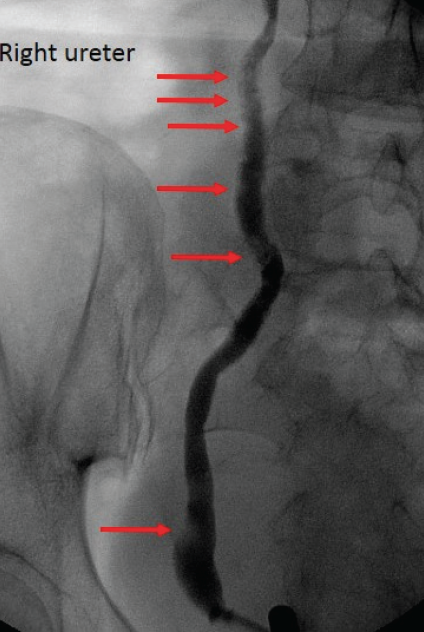

Figure 2. Multiple small lucent defects in the right ureter, indicated by red arrows.

Diagnostic testing. Given her 1-year history of gross hematuria and severe anemia, a hematuria workup was initiated on an inpatient basis. An excretoryphase computed tomography urogram demonstrated numerous small filling defects in the bilateral ureters and urinary bladder. Given these findings, she underwent a retrograde pyelogram that confirmed the bilateral filling defects (Figures 1 and 2). A subsequent diagnostic ureteroscopy revealed multiple smooth-walled, cyst-like protrusions into the ureters bilaterally, consistent with ureteritis cystica.